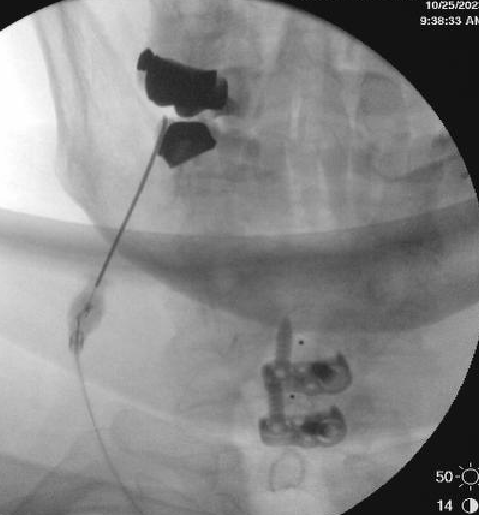

Haha he was wondering if worsening stenosis or listhesis was an issue, thought the slip might need surgery with axial pain. Just showing a bad slip, can still be treated with good results, don't forget about endplates.Basically Rolo’s saying don’t worry about it but look at what I did 😆

I know I was just messin 😉Haha he was wondering if worsening stenosis or listhesis was an issue, thought the slip might need surgery with axial pain. Just showing a bad slip, can still be treated with good results, don't forget about endplates.

This is now off-topic but - What is your general experience with Intracept for stable spondylolisthesis? Was this guy presenting as a typical "anterior column" pain? Or was it non-specific and he happened to have Modic? I have a 30 year old with history of scoliosis and surgery from L2 up, who has old pars fractures at L5 with stable spondy at L5-S1 and type 1 Modic. Failed MB RFA and ESI. All axial pain with occasional left leg pain but axial is main complaint. His symptoms are fairly non-specific, but he's a normal guy. Hesitant to offer Intracept, but absolutely do not want to send him for a fusion since he's already fused at L2 and I think it will just be a cascade.Haha he was wondering if worsening stenosis or listhesis was an issue, thought the slip might need surgery with axial pain. Just showing a bad slip, can still be treated with good results, don't forget about endplates.

No hesitation with stable spondy. Even if there's a few mm movement on flex ext but radicular component is mild/intermittent, I still do, just tell them they may have higher chance of radiculitis, though I haven't seen that to be the case. Outcomes still mirror literature.This is now off-topic but - What is your general experience with Intracept for stable spondylolisthesis?

Pain was more "always there", worse with activity, morning stiffness, transitioning from different positionsWas this guy presenting as a typical "anterior column" pain?

I think he's a good candidate. Young people with Modic 1 usually do well, especially since you've ruled out other causesOr was it non-specific and he happened to have Modic? I have a 30 year old with history of scoliosis and surgery from L2 up, who has old pars fractures at L5 with stable spondy at L5-S1 and type 1 Modic. Failed MB RFA and ESI. All axial pain with occasional left leg pain but axial is main complaint. His symptoms are fairly non-specific, but he's a normal guy. Hesitant to offer Intracept, but absolutely do not want to send him for a fusion since he's already fused at L2 and I think it will just be a cascade.